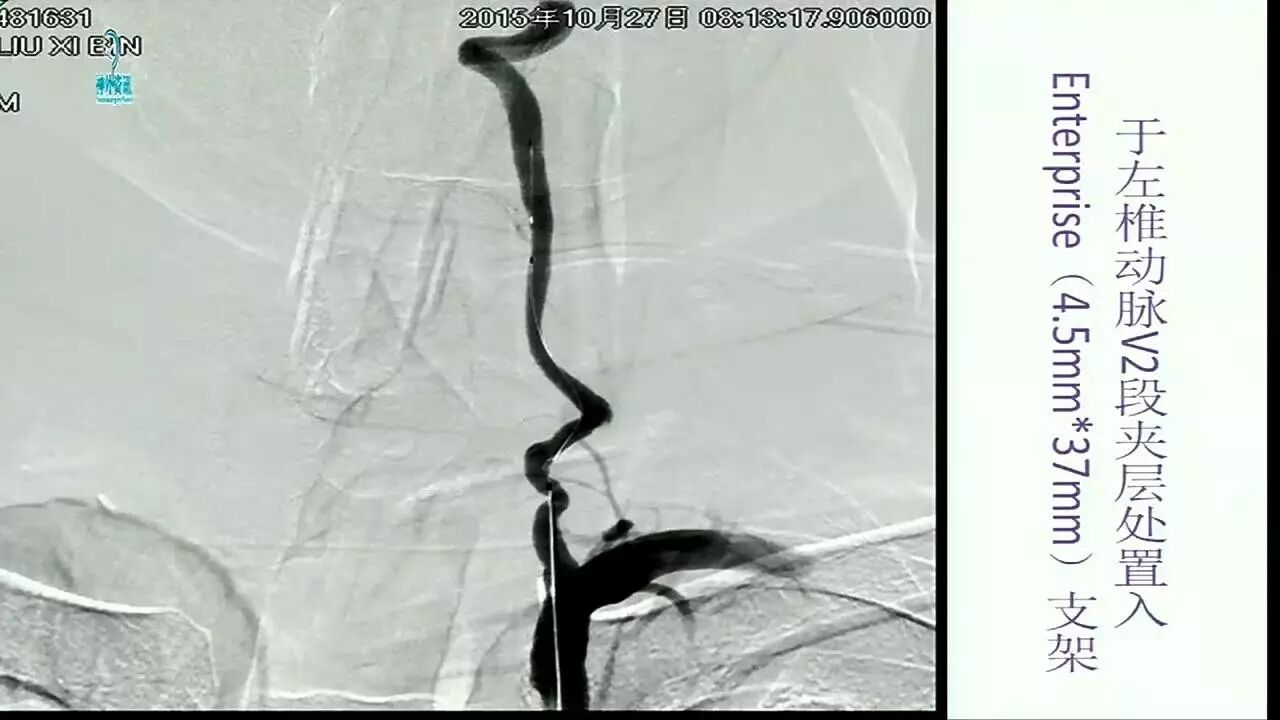

Enterprise支架在缺血性脑血管病中的应用